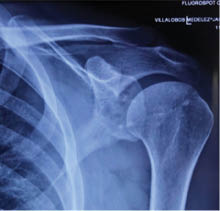

Imagen: se realizó una radiografía con proyección anteroposterior (Figura 1), y una resonancia magnética simple de hombro izquierdo (Figuras 2 y 3) y se realizó el diagnóstico de luxación glenohumeral, inestabilidad anterior de hombro, lesión de Bankart y lesión de Hill-Sachs.

En las imágenes tomadas antes del procedimiento quirúrgico se observa, en la primera radiografía simple de hombro izquierdo en proyección anteroposterior, una luxación de la articulación glenohumeral, mientras que en la resonancia magnética simple (cortes axial y coronal), se detecta una lesión de Hill-Sachs y una lesión de Bankart, las cuales de acuerdo con la literatura son característica en los pacientes con luxación glenohumeral e inestabilidad anterior de hombro.

Figura 1